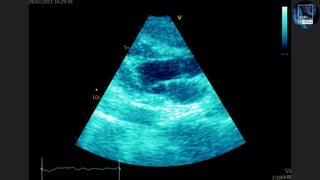

The document discusses the potential of echocardiography in managing cardiac arrest, emphasizing its non-invasive and painless nature for bedside assessments. It highlights the importance of recognizing the causes of cardiac arrest, such as hypovolaemia and tension pneumothorax, and the need for proper training of healthcare staff. Additionally, it provides resources for further learning, including social media and a dedicated website.